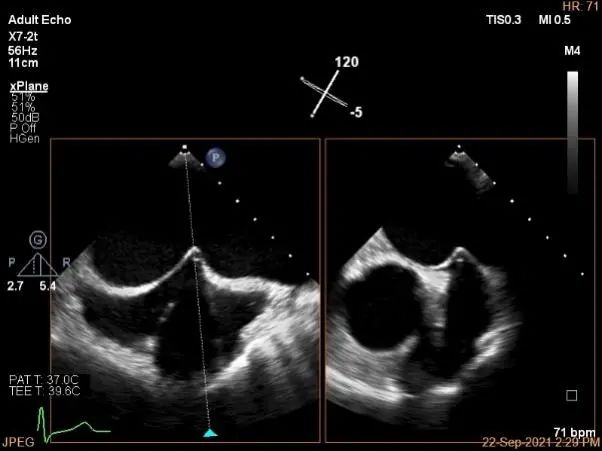

房间隔穿刺点选择

穿刺高度:4.3cm